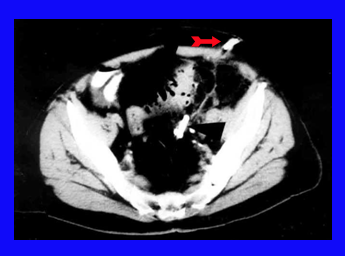

האבחנה היא בטומוגרפיה ממוחשבת או באולטרה-סאונד שבהם אפשר להדגים את המורסה ולראות את המעי המעובה, חסר המבנה השקי (סקולרי) (תצלומים 14.6ו- 15.6).

בחולים שהתפתחו בהם מורסות עקב התנקבות הסעיף הדרך המומלצת לניקוז היא בגישה מל-עורית (Percutaneous) בהנחיית טומוגרפיה ממוחשבת או אולטרה-סאונד. לאחר הניקוז יש להשאיר נקז במקום (תצלום 16.6). מורסות אגניות אפשר לנקז בגישה חלחולתית. בחולים שבהם הניקוז המל-עורי נכשל, צריך לנקז את המורסה בניתוח.

סיבוכי דלקת סעיפי הכרכשת ודלקת הצפק